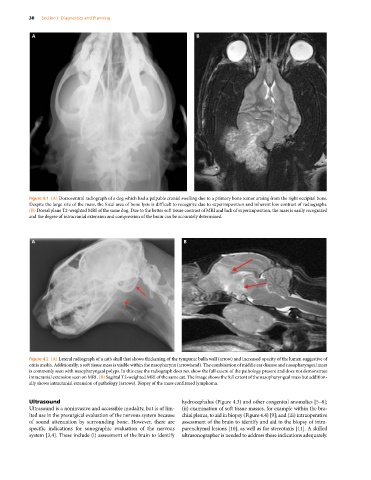

Figure 4.1 (A) Dorsoventral radiograph of a dog which had a palpable cranial swelling due to a primary bone tumor arising from the right occipital bone.

Despite the large size of the mass, the focal area of bone lysis is difficult to recognize due to superimposition and inherent low contrast of radiographs.

(B) Dorsal plane T2‐weighted MRI of the same dog. Due to the better soft tissue contrast of MRI and lack of superimposition, the mass is easily recognized

and the degree of intracranial extension and compression of the brain can be accurately determined.

Figure 4.2 (A) Lateral radiograph of a cat’s skull that shows thickening of the tympanic bulla wall (arrow) and increased opacity of the lumen suggestive of

otitis media. Additionally, a soft tissue mass is visible within the nasopharynx (arrowhead). The combination of middle ear disease and nasopharyngeal mass

is commonly seen with nasopharyngeal polyps. In this case the radiograph does not show the full extent of the pathology present and does not demonstrate

intracranial extension seen on MRI. (B) Sagittal T2‐weighted MRI of the same cat. The image shows the full extent of the nasopharyngeal mass but addition-

ally shows intracranial extension of pathology (arrows). Biopsy of the mass confirmed lymphoma.